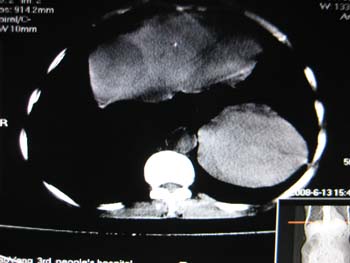

女,65岁,左上腹痛。

肝脏占位  脾脏及胰腺病变   请提供病史

肝脾胃左肾胰都显示不正常啊

病史不详,肝、脾、胰都有占位,谁是原发?

胰腺癌伴脾脏侵犯并肝内转移可能性大  建议增强扫描  否则没有确凿的依据

考虑姨尾癌,腹膜后转移\\肝转移

没有病史,没有强化,那就只有猜了,我看病灶很像肝、脾及腹腔多发脓肿,这只是我的意见,

图像欠清,病灶与胃脾胰肾上腺关系显示欠清,建议增强,肝脏考虑转移瘤.

多脏器占位,腹膜后淋巴结增大,淋巴瘤?建议增强扫描